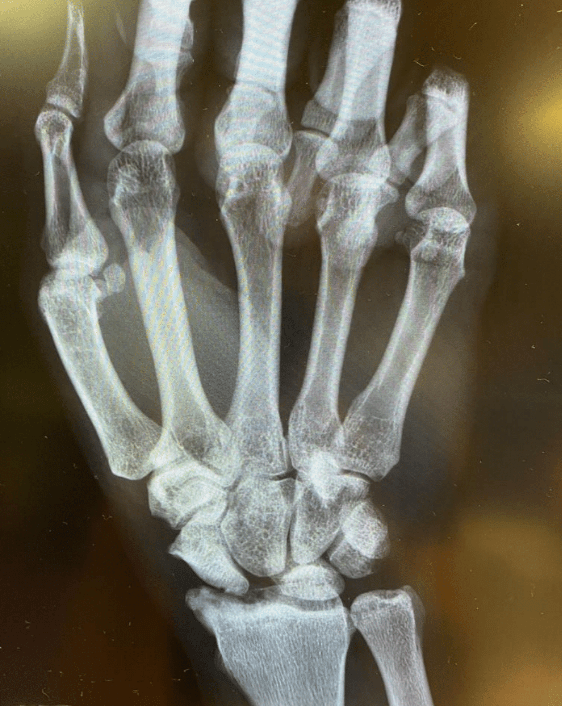

What’s the Diagnosis? Gepost op 2 november 202029 oktober 2020 door netwerkvsseh What’s the Diagnosis? By Dr. Jacob Martin @emdaily.cooperhealth.org Dit delen: Delen op X (Opent in een nieuw venster) X Share op Facebook (Opent in een nieuw venster) Facebook Delen op LinkedIn (Opent in een nieuw venster) LinkedIn E-mail een link naar een vriend (Opent in een nieuw venster) E-mail Afdrukken (Opent in een nieuw venster) Print Vind-ik-leuk Aan het laden... Gerelateerd